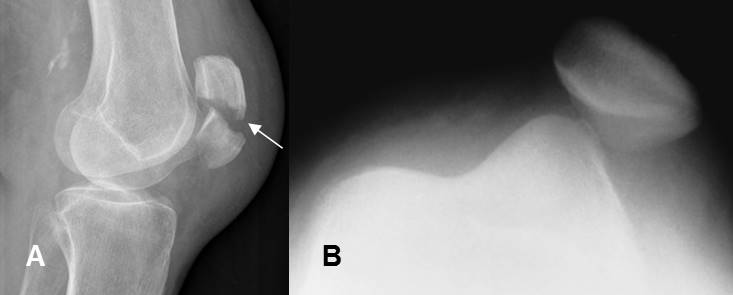

- Dirección: Una misma fuerza produce diferente tipo de lesión, dependiendo de la dirección en que actúe. Ej: Un trauma directo en la parte anterior de la patela, puede causar su fractura y uno en la parte medial, puede producir su luxación. (Fig 1).

Fig 1. Lesiones según la dirección del impacto.

A: Rx lateral. Fractura transversa, en el tercio medio de la patela.

B: Rx tangencial. Luxación lateral de la patela.